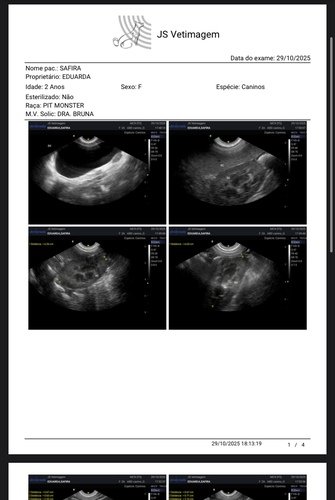

Alguns meses atrás realizamos exames e biópsia que teve como resultado hemangioma, um tumor benigno que poderia virar um tumor maligno chamado emangiossarcoma. Como são vários nódulos pelo corpo dela, existia chance de algum deles já ser maligno. Então nossa saída era fazer outros exames para poder começar uma eletroquímio, porém na ultrassom encontramos uma neoplasia de 14cm na parede do estômago, cisto no ovário esquerdo e pancreatite.

Já fizemos a gastrectomia para biópsia e castração, para agora acompanhar com ultrassom. Para um cachorro de grande porte e uma cirurgia delicada, o custo que já era alto ficou ainda maior. Felizmente está tudo correndo bem, ela está ótima para alguém que operou. Hoje, clinicamente ela está bem e não apresenta nenhum sintoma, então é o melhor momento para tratar a cuidar dela. Estamos com um veterinário de muita confiança para observar cada mudança com ela e aplicar vitaminas que são importantes para o imunológico dela. Mas ainda temos que terminar de pagar os custos dessa primeira primeira parte que passamos. Não pretendemos atingir metas, mas qualquer ajuda será recebida com muita gratidão! Se começarmos temos que ir até o final, pelo bem e carinho que temos por ela. Toda ajuda é bem vinda!